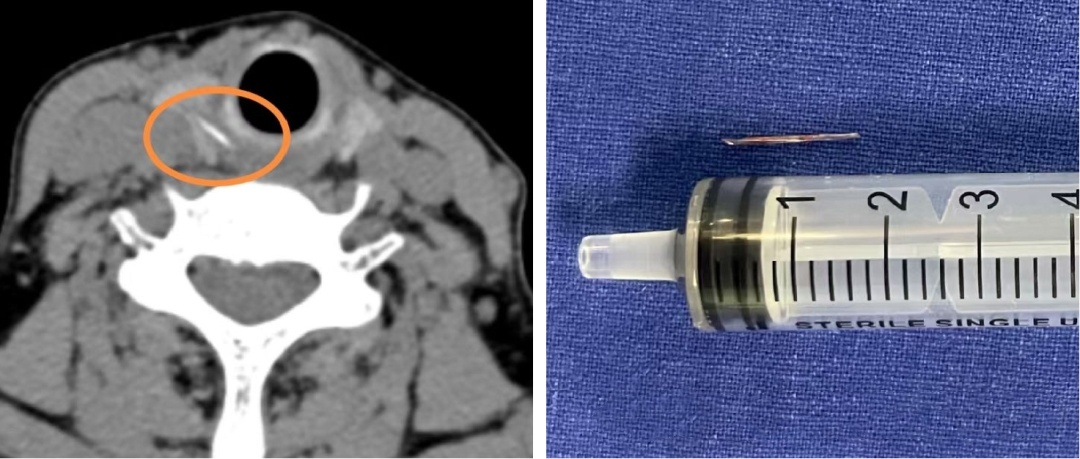

耳听为虚眼见为实,刘阿姨意识到问题的严重性,起身去了CT室。影像结果证实了之前的猜测:

在右侧甲状腺位置,发现了一条索状的高密度异物影,极有可能是鱼刺穿透食道壁,扎进了甲状腺。

情况变得十分棘手。仅仅依靠内窥镜做微创手术,显然无法取出这根“逃逸”的鱼刺。经过审慎评估,邹文焘决定为刘阿姨实施全麻下颈侧切开术,最终成功从右侧甲状腺中,取出了一枚长约1.5厘米的鱼刺。探查还发现,周围的食道黏膜有轻度肿胀,便对创面作了仔细消毒。术后,刘阿姨喉咙的疼痛明显减轻,经过抗炎治疗,颈部的切口愈合良好。